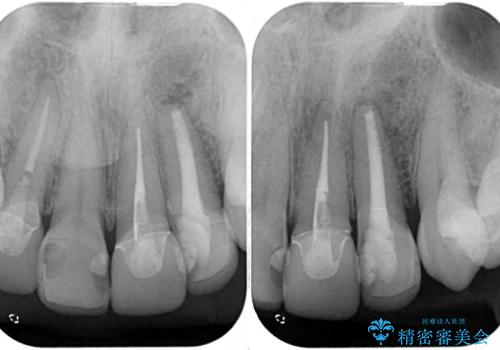

- 前歯が折れてしまい、ブリッジによる補綴治療を希望して来院された患者様です。

折れている前歯は抜歯をし、痩せてしまう歯肉は移植術により増大させることで審美面を回復した後、オールセラミックブリッジにて補綴することとしました。

インプラントかブリッジか悩むところでしたが、既に治療されている前歯のクラウン周りの変色が気になっていたため、ブリッジにより色調を合わせたオールセラミックを装着することを選択しました。